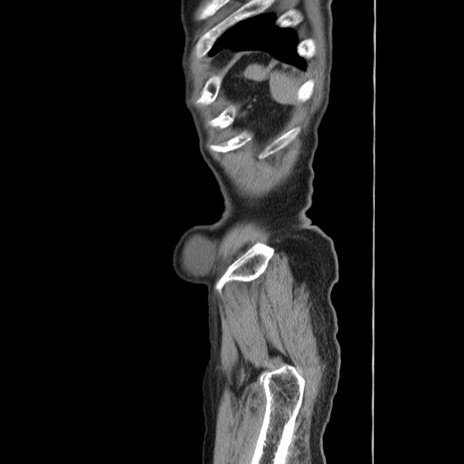

症例24(矢状断像)

【症例】80歳代男性

【主訴】左側腹部痛、嘔吐

【現病歴】本日早朝より左腹部に痛みあり。昼頃嘔吐認めたため、救急要請。

【既往歴】直腸癌(Mile手術)、胆摘

【身体所見】意識清明、BT 35.9℃、BP 221/93mmHg、SpO2 97%(RA) 、腹部:左ストーマ周囲に限局性の腹部膨隆あり。 膨隆部自発痛・圧痛あり・軟。

【データ】WBC 7700、CRP 0.09